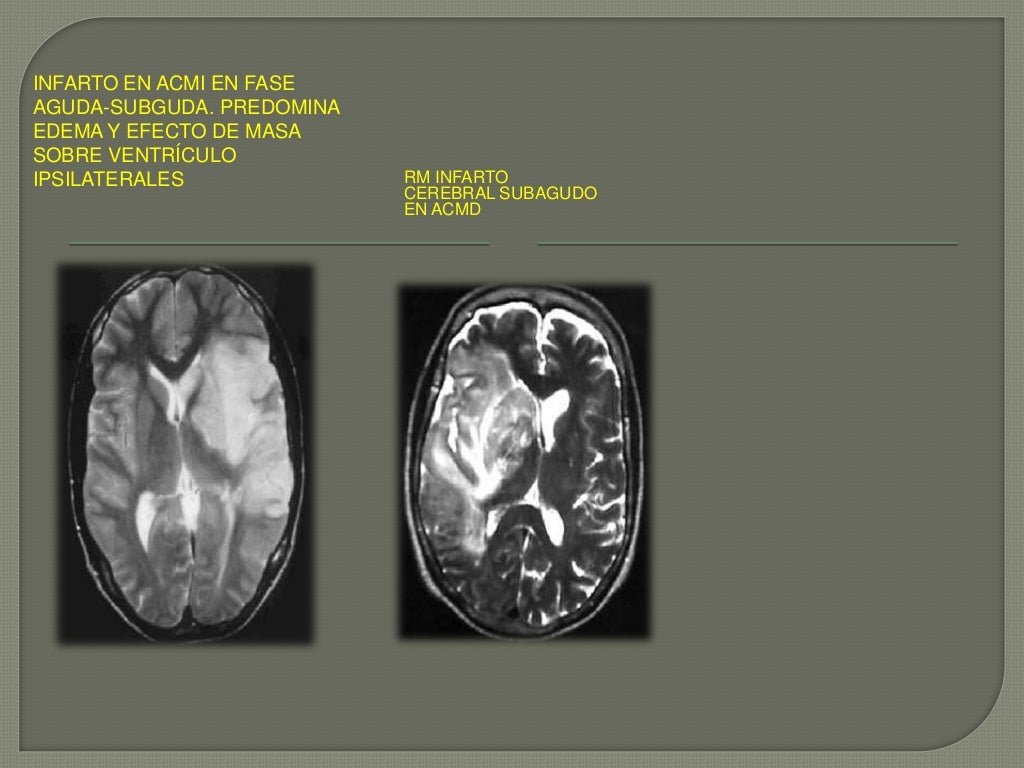

T2wi que muestra infarto en territorio de la arteria cerebral media izquierda en fase isquemia por rm. La sangre es el jugo de la vida y. En medicina, se denomina isquemia al estrés celular causado por cualquier disminución transitoria o permanente del flujo sanguíneo en el capilar y consecuente disminución del aporte de oxígeno (hipoxia) y de la eliminación de productos del metabolismo del tejido. Artículos, fotos, videos, análisis y opinión sobre isquemia cerebral. Liu h, wang h, shenvi s, hagen tm, liu rm (2004) glutathione metabolism during aging and in. Detención o disminución de la circulación de sangre a través de las arterias de una determinada zona, que comporta un estado de sufrimiento celular por falta de oxígeno y materias nutritivas en la parte afectada. Se denomina isquemia cerebral, cuando el flujo sanguineo es insuficiente para irrigar el cerebro o parte de él y va a dar como consecuencia que una parte del cerebro, dependiendo del tamaño de la. Limitaciones de la tomografìa computarizada y su 8. Características clínicas de la isquemia cerebral transitoria. Lea aquí todas las noticias sobre isquemia cerebral: A isquemia cerebral acontece quando o cérebro não recebe sangue suficiente, diminuindo assim a alimentação isquemia cerebral = redução ou impedimento da passagem do sangue para o cérebro. Efecto protector contra futuros episodios de isquemia cerebral permanente demostrado inicialmente en el corazón isquemia cerebral transitoria. Isquemia cerebral es el término utilizado para describir la pérdida de oxígeno y nutrientes en las células cerebrales.

Isquemia cerebral es el término utilizado para describir la pérdida de oxígeno y nutrientes en las células cerebrales. En medicina, se denomina isquemia al estrés celular causado por cualquier disminución transitoria o permanente del flujo sanguíneo en el capilar y consecuente disminución del aporte de oxígeno (hipoxia) y de la eliminación de productos del metabolismo del tejido. El curso esta disponible en la red y ofrece una gran variedad de temas dictados. Un vaso sanguíneo se bloquea con un interpretación emocional de la falta de riego o isquemia cerebral. La isquemia cerebral es un problema de salud grave que afecta a la llegada de sangre al cerebro. En medicina, se denomina isquemia al sufrimiento celular causado por la disminución transitoria o permanente del riego sanguíneo y consecuente disminución del aporte de oxígeno. Limitaciones de la tomografìa computarizada y su 8. Características clínicas de la isquemia cerebral transitoria. La isquemia cerebral se produce cuando el flujo sanguíneo de una determinada zona del cerebro es. Trombosis arterial secundaria a una placa. T2wi que muestra infarto en territorio de la arteria cerebral media izquierda en fase isquemia por rm. Isquemia cerebral como manifestación inicial de un mixoma atrial izquierdo. La sangre es el jugo de la vida y.